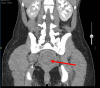

Vaginal agenesis is part of a group of anomalies, referred to as Mullerian anomalies due to their embryologic origin, in which there is a congenital absence of the vagina. We present a unique case in which a 20-year-old female presented to the Emergency Department with cyclical abdominal pain and primary amenorrhea. The original assessment showed a probable imperforate hymen; however, it was later found that she likely had vaginal agenesis. Vaginal agenesis is a rare disease, but it is prevalent enough that it should be kept at the forefront of the differential diagnosis in a woman with primary amenorrhea and recurring pain. We also highlight the importance of patient education in general, but categorically to sexual health.